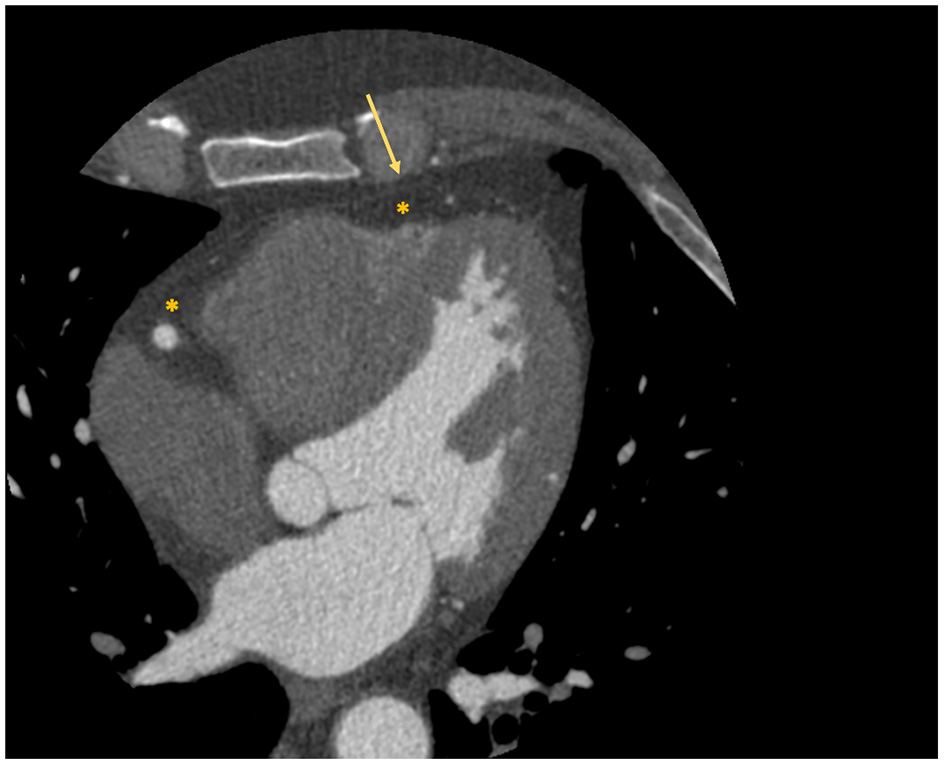

Interest has grown toward the correct quantification and analysis of the epicardial adipose tissue (EAT), namely the fat layer located between the myocardium and the visceral pericardium (Figure 2), due to the emerging evidence that identified its role in atherosclerosis development and consequently in obstructive CAD (21). An even more important role in atherosclerosis seems to be played by the pericoronary adipose tissue (PCAT), the EAT layer directly surrounding the coronary arteries.

Figure 2

Localization of epicardial adipose tissue at cardiac CT scan. The figure depicts an example of visualization of the epicardial adipose tissue with a cardiac CT scan. The asterisk identifies the hypodense area of adipose tissue; while the arrow identifies the visceral pericardium.